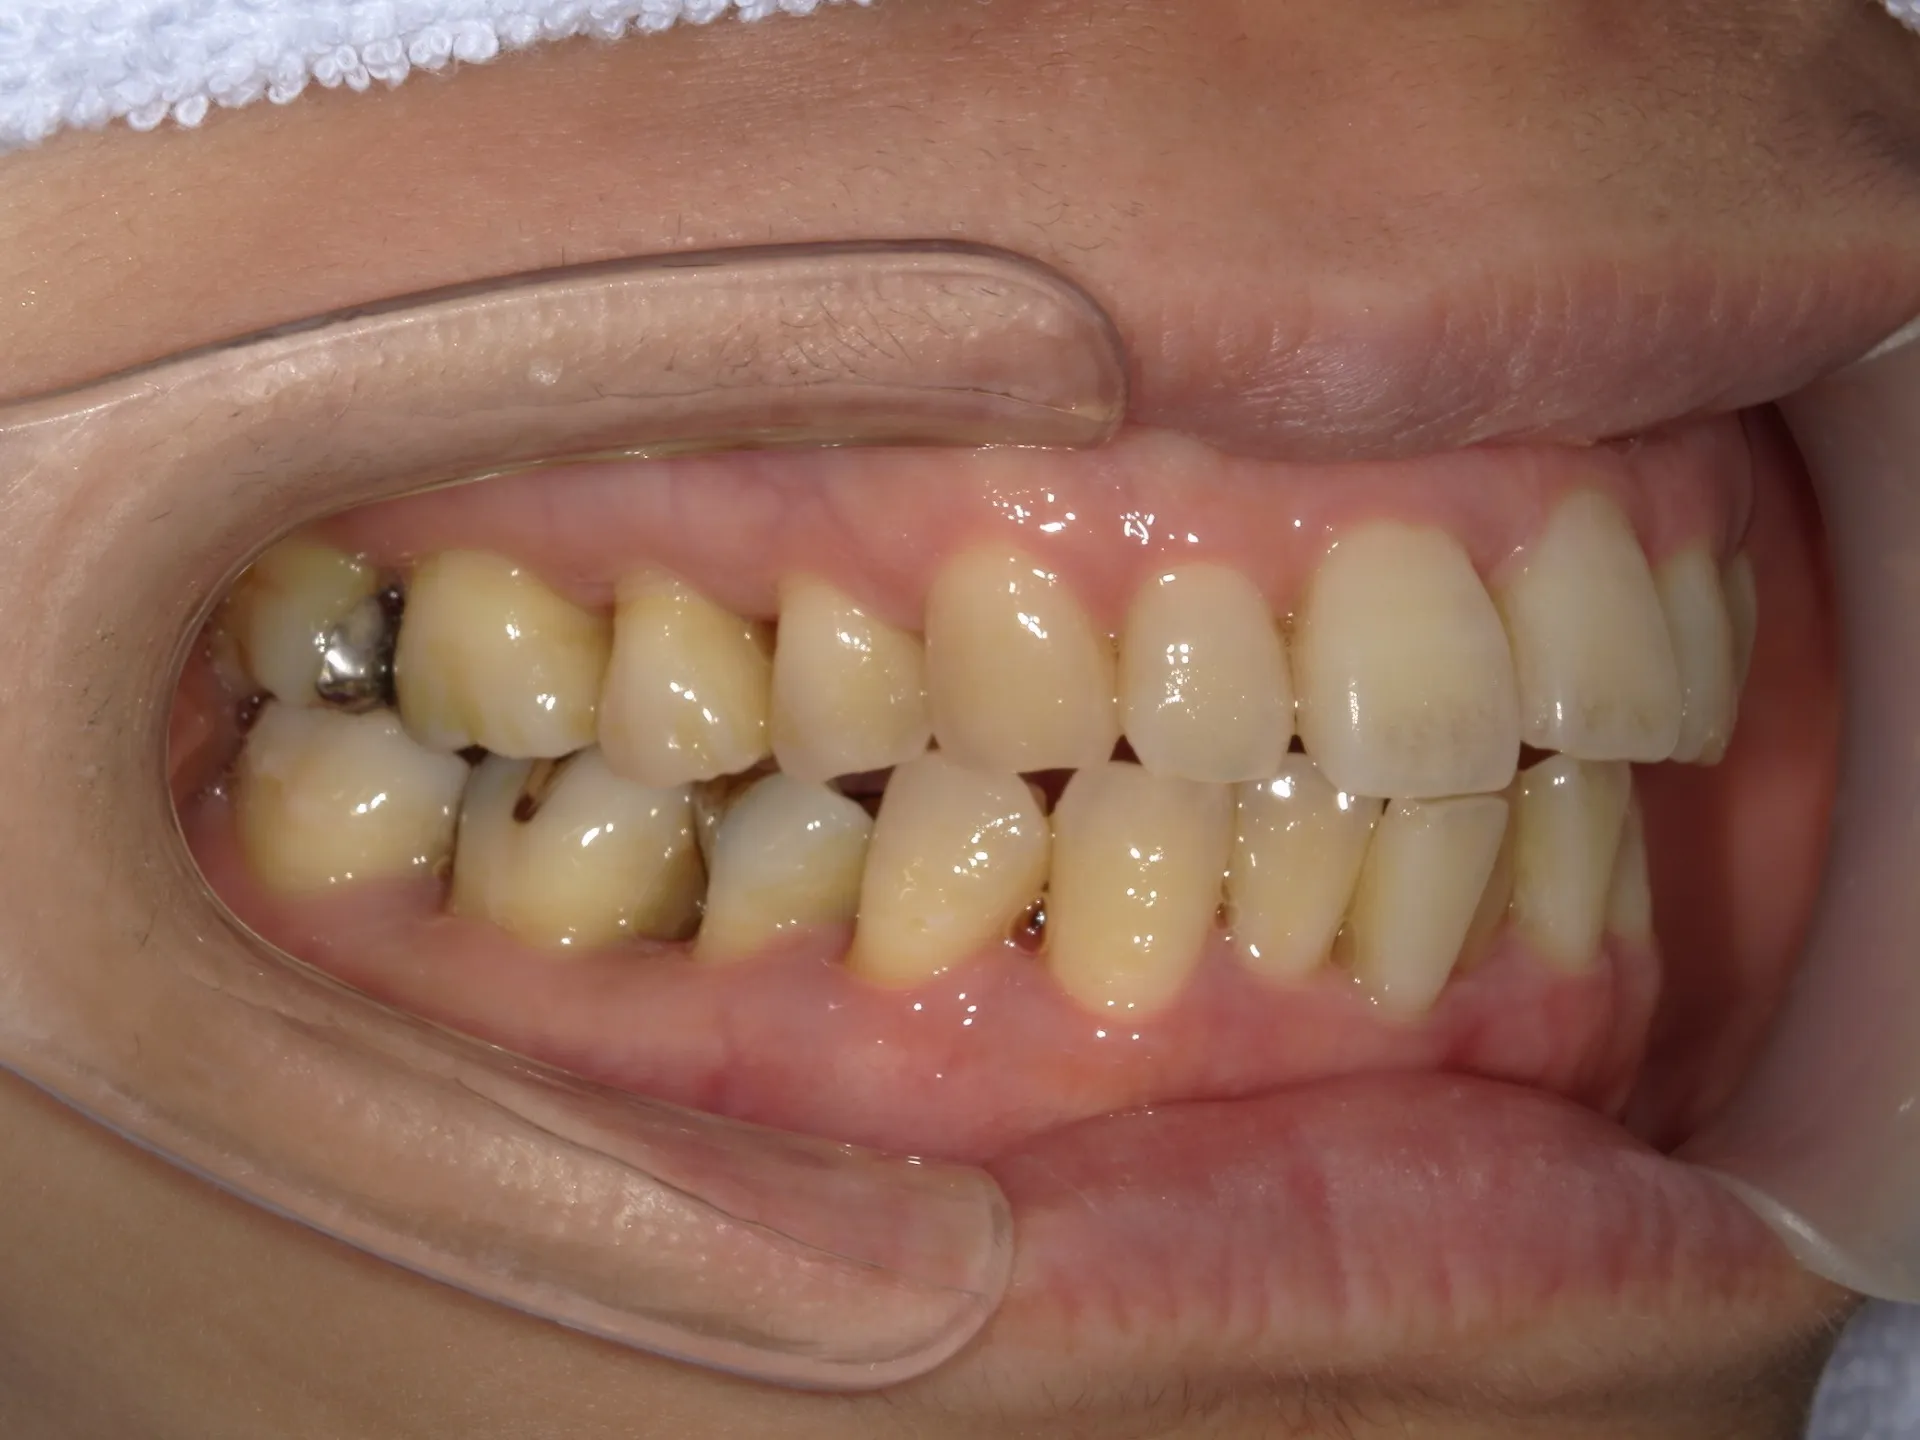

当院では矯正治療と歯周治療を平行して行うことにより矯正治療を進めていけることができました。

しかしながら、今回の治療途中で歯茎が腫れるなどの影響もあり、歯周治療中の矯正治療はリスクであることは患者様にも初回の段階で説明していることもあり、患者様もこの状態の歯並びで満足しており、歯を残すためにも今回は矯正治療を中断する希望をされました。